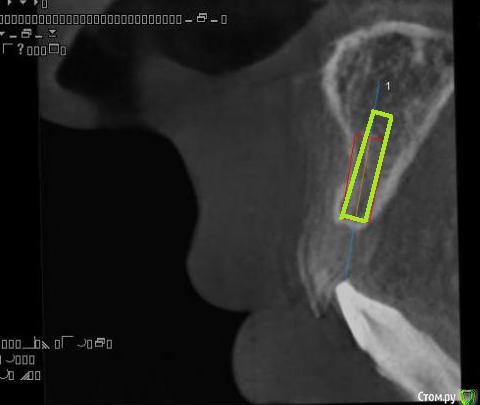

alekszander Опубликовано 11 февраля, 2016 Поделиться Опубликовано 11 февраля, 2016 (изменено) Какую лучше выбрать НКР?Первая мысль - одномоментно имплант + "сосидж".Вторая блок.Ламинат, но нечем сделать забор трансплантата.Мягкотканная только, но как-то не айс...Прошу совета, дабы понять возможность наименьшей инвазии. Изменено 11 февраля, 2016 пользователем alekszander Ссылка на комментарий

ILGAMSA Опубликовано 11 февраля, 2016 Поделиться Опубликовано 11 февраля, 2016 Очень редкая ситуация сделать вот так http://s008.radikal.ru/i305/1602/4d/a0829d82adcb.jpg Я бы её не упустил 12 Ссылка на комментарий

andr99 Опубликовано 11 февраля, 2016 Поделиться Опубликовано 11 февраля, 2016 Присоединюсь к krikov'у и carloss'у.Расщепленный лоскут + ССТ, возможно с остеотомами.Какой диаметр имплантата на КТ? 1 Ссылка на комментарий

alekszander Опубликовано 12 февраля, 2016 Автор Поделиться Опубликовано 12 февраля, 2016 Спасибо всем огромное! Будем или расщеплять или как Ильгам предложил попробую. Сделаю когда постараюсь выложить отчёт. Имплант Дентиум стоял 3.6 на 10. Ссылка на комментарий